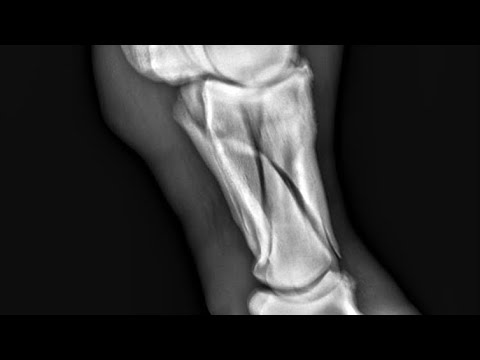

Metatarsal fracture fixation in horse | Velcast casting tape | fracture | Dr Ashwani Bassan |See more

Fracture management in horse with fiberglass cast.

Fiberglass cast for fracture repair in horse.See more